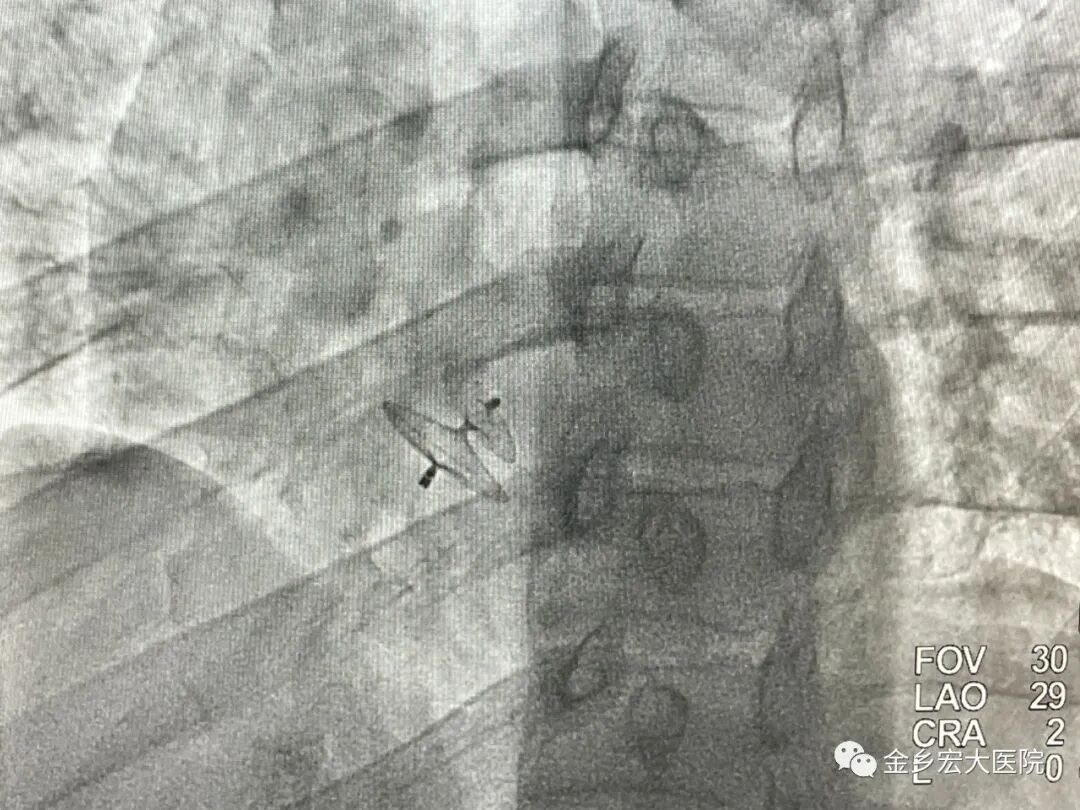

金乡宏大医院成功完成一例卵圆孔未闭介入封堵术